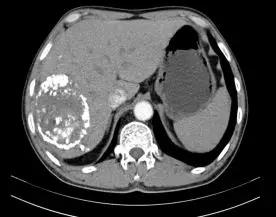

60歲的劉大爺5個月前右上腹部出現(xiàn)疼痛,在當?shù)蒯t(yī)院檢查確診為晚期巨大肝癌,去其他醫(yī)院檢查后仍然是同樣的結(jié)果,醫(yī)生說已經(jīng)沒有治療的價值,建議他回家好好享受剩下的日子。就在他絕望的時候,同村的人向他介紹說我院普外科對待病人“肝膽相照”。劉大爺抱著試試看的心態(tài)住進我院普外科,經(jīng)過詳細檢查發(fā)現(xiàn),右肝巨大腫物約為12×11×11厘米且伴仔瘤,肝硬化,左半肝變小,確診為原發(fā)性晚期巨大肝癌。

栓塞術(shù)中顯示的肝部腫瘤與栓塞術(shù)后CT顯示的腫瘤對比

“這種情況不宜切除右半肝臟,因為左半肝體積小,余肝不能代償,切除后會導致肝功能衰竭,危及生命。必須先行介入治療,把供應肝臟腫瘤的血管堵死,‘餓死’癌細胞,使癌瘤縮小,左肝代償增大,待肝癌降期后再行手術(shù)治療,效果會比較好,也比較安全。”濰坊市市立醫(yī)院普外科主任醫(yī)師遲景濤分析說。

劉大爺住院期間共經(jīng)過“經(jīng)皮經(jīng)股動脈穿刺肝動脈選擇性造影并肝癌灌注化療栓塞術(shù)”介入治療兩次,巨大肝癌明顯減小,普外專家團隊擇期為其進行了手術(shù),而且又成功實施了肝第Ⅶ段、第Ⅵ段切除手術(shù)。劉大爺康復出院時精神抖擻,滿面笑容,還滿意的說癌癥再厲害也敵不過濰坊市市立醫(yī)院普外科專家的手術(shù)刀!